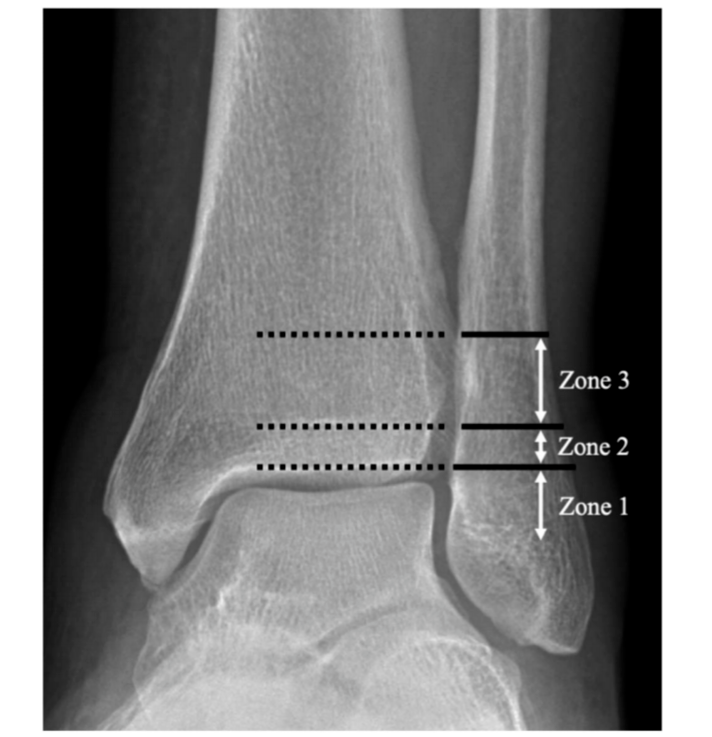

图2Danis-Weber B型骨折,根据近端骨折块最远端位置分区。1区定义为骨折块最远端位于胫骨远端关节面平面以下;2区为位于胫骨远端骺线闭合瘢痕与远端关节面之间;3区为骺线闭合瘢痕以上。

图3 分区示意图。

共有191例1区(止于胫骨远端关节平面下方)损伤,57处2区(止于胫骨远端骨骺线闭合瘢痕和胫骨远端关节面之间)损伤,39处3区(止于胫骨远端骨骺线闭合瘢痕以上)损伤。其中,17% (33名患者)的1区、42% (24名患者)的2区和74% (29名患者)的3区骨折合并下胫腓韧带损伤。

2区与1区相比,韧带联合损伤的相对风险为2.4 (P,0.001),3区与1区相比为4.3 (P,0.001),3区与2区相比为1.8 (P = 0.002)。观察者间和观察者内的可靠性非常好(k = 0.86,0.94)。

[Results: There were 191 zone 1 (ending below the plafond) injuries, 57 zone 2 (ending between the physeal scar and the plafond) injuries, and 39 zone 3 (ending above the physeal scar) injuries. Of these, 17% (33 patients) of zone 1, 42% (24) of zone 2, and 74% (29) of zone 3 fractures had syndesmotic injuries. The relative risk of syndesmotic injury of zone 1 compared with zone 2 was 2.4 (P , 0.001), zone 1 to zone 3 was 4.3 (P , 0.001), and zone 2 to zone 3 was 1.8 (P = 0.002). The interobserver and intraobserver reliability was excellent (k = 0.86, 0.94).]